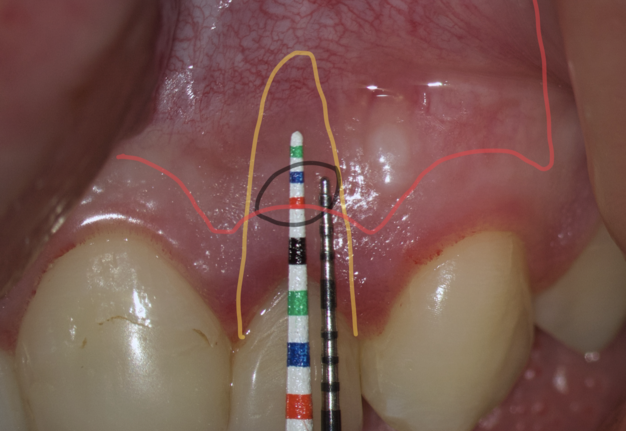

The most popular paramarginal or submarginal flap is the one designed by Clifford Ochsenbein and Raymond G. Luebke (1974) [4, 5]. The Ochsenbein-Luebke flap is formed by a scalloped horizontal sub-marginal incision placed within the attached gingiva, which follows roughly parallel to the contour of the gingival margin. The horizontal incision continues with two vertical releasing incisions [6]. These vertical incisions extend from a point 1 to 2 mm short of entering the mucobuccal fold to a point on the attached gingiva approximately 3 to 5 mm above or below the marginal gingiva and the sulcus depth (Figs 1 and 2) [7, 8].

The submarginal flap is only to be used, when there is a broad zone of attached gingiva with a minimum of 2 mm [9]. The width of the attached gingiva is then calculated on the basis of the distance from the base of the sulcus to the linea girlandiformis (mucogingival junction) [6]. Consequently, the incision must be placed at least 2 mm from the depth of the gingival sulcus. Extensive periodontal probing should be done to establish the depth of the gingival sulcus before the incision is made [10]. Periodontal probing should be conducted not only around the causative tooth but also in the adjacent teeth.

Sometimes the frenulum of the upper lip is massive and for avoid its dissection, it is permissible to perform a submarginal flap with one vertical incision located more distally. It is worth recognizing that this approach is applied to a root with medium length on which microsurgery is performed (Figs 3 and 4).